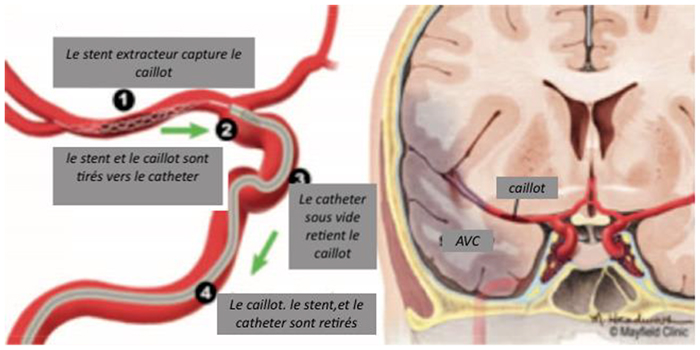

Lors de cette intervention réalisée par des radiologues spécialisés, un cathéter est inséré dans le réseau artériel, généralement par une piqure dans l’aine, et guidé jusqu’aux artères du cerveau, où il permet de retirer mécaniquement le caillot qui bloque la circulation sanguine à l’aide d’un stent et/ou d’un cathéter d’aspiration. Cette procédure vise à restaurer le flux sanguin vers la zone du cerveau affectée, minimisant ainsi les dommages cérébraux et améliorant les chances de récupération. L’intervention est réalisée sous contrôle radiologique en temps réel.

L’intervention : explications